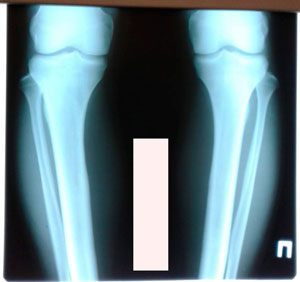

Исходник- 29 лет

Диагноз: варусная деформация голеней.

Жалобы на боли в коленях.

Дата операции - 19.11.2019г.